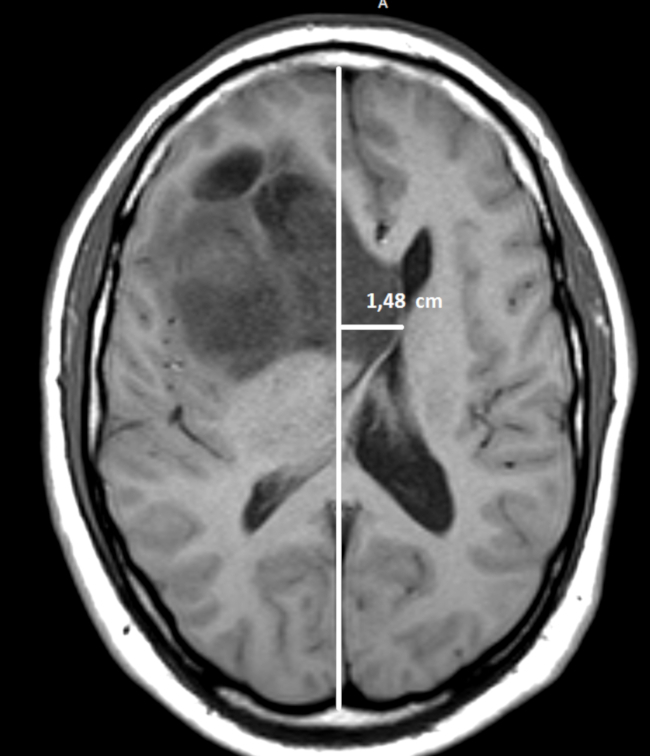

Este desplazamiento puede mesurarse por TC o resonancia magnética (RM) en cortes axiales, tomando como referencia la posición de las principales estructuras mediales como: septum pellucidum, hoz del cerebro, III ventrículo o glándula pineal.8,9 Para medirlo, se traza una línea recta que pase a través de la hoz cerebral desde su inserción rostral hasta la inserción dorsal en la tabla interna.9,10,11

En caso de que una lesión genere efecto de masa y desplace la línea media, se desplazarán las estructuras mediales anteriormente mencionadas. Para mesurar ese desplazamiento, se traza una línea perpendicular a la línea media hasta donde se encuentra el septum pellucidum o la hoz cerebral y se mide la distancia (►Fig. 2).9,10,11

Un desplazamiento de la línea media mayor a 0,5 cm es un predictor de mal pronóstico para la evolución neurológica de pacientes con traumatismos de cráneo internados en terapia intensiva.12,13